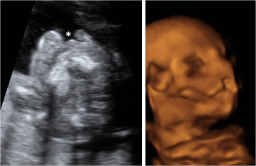

A lo largo del embarazo, el médico te recomendará una serie de pruebas diagnósticas para asegurarse que tu hijo se desarrolla correctamente, como la ecografía. Otras solo se prescriben cuando el ginecólogo sospecha que algo puede ir mal y necesita más datos para corraborarlo, como la amniocentesis o el control del bienestar fetal. Te contamos cómo y cuándo se realizan.